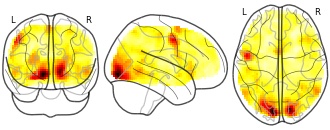

"name": "VBM_HeterogeneityMap",

"description": "Abnormal gray matter in BPD. Brain regions with significant heterogeneity (i.e. between-study variance) in the comparison of patients with BPD and healthy controls. Results are thresholded at at p<.005 & k>20. Note: Results are based on meta-analysis of group comparisons. Note2: Results were updated (see Erratum for this publication)",

"add_date": "2016-01-21T18:23:32.131003+01:00",